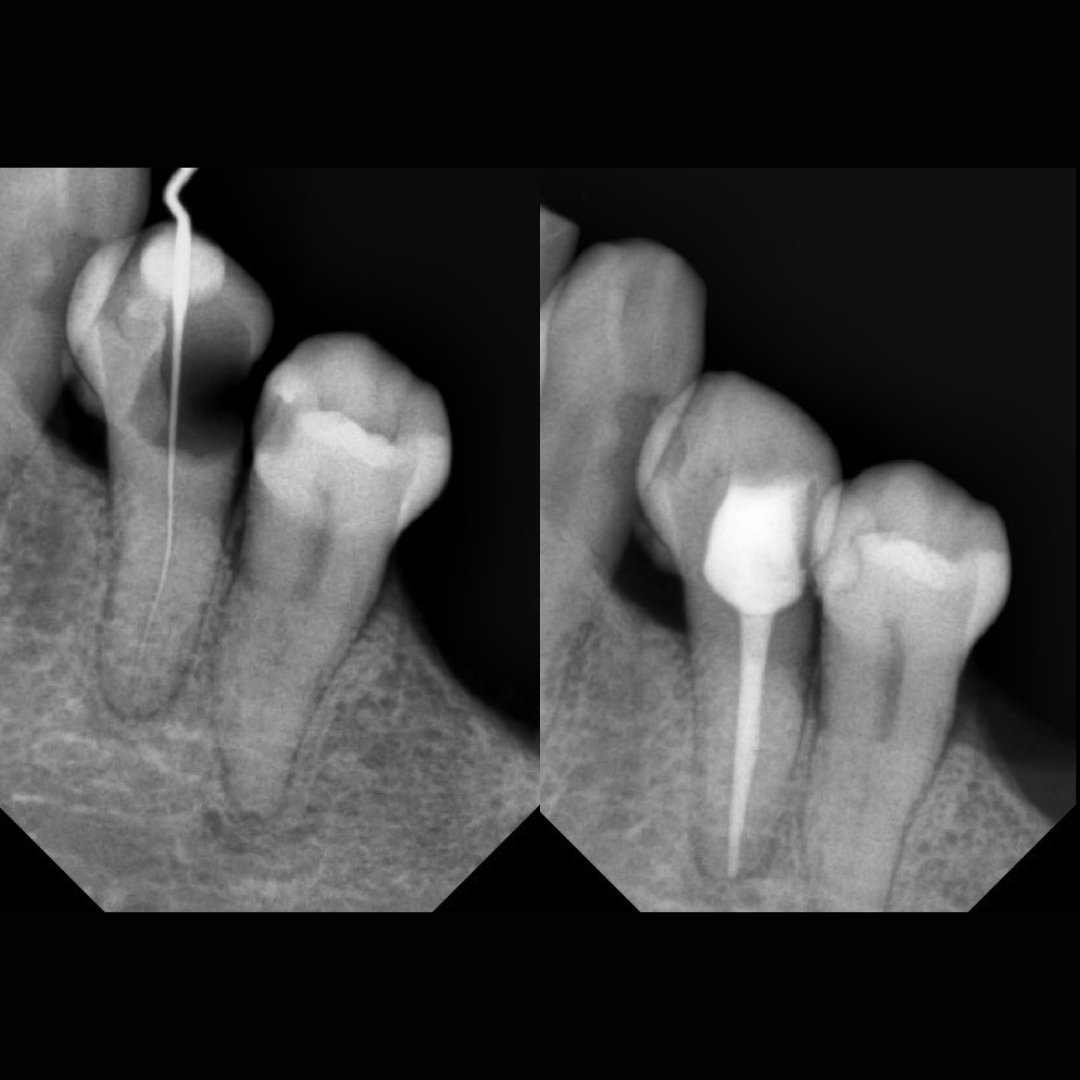

Before After Perawatan Saluran Akar (PSA) di Klinik Utama Pondok Gigi Jakarta

Transformasi nyata setelah perawatan saluran akar (PSA) di Klinik Utama Pondok Gigi Jakarta. Dari gigi rusak dan nyeri hingga kembali sehat dan berfungsi normal. Dikerjakan oleh dokter gigi profesional dengan teknik endodontik modern dan alat berteknologi tinggi untuk hasil maksimal.